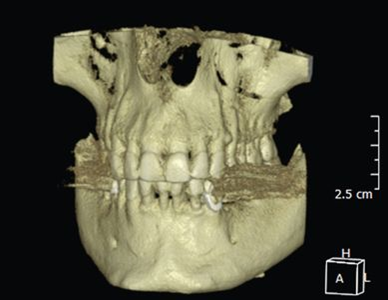

Abb. 1: Die Daten können in verschiedenen Ebenen wiedergegeben werden.

Das Grundgerüst der fertig rekonstruierten Datensätze sind die Voxel (engl.: volumetric element). Sie stellen zugleich die kleinste Baueinheit dar und sind bei der DVT in aller Regel isotrop, also würfelförmig. Die CT hingegen liefert oftmals – abhängig von der selektierten Schichtdicke – anisotrope Voxel. Durch weitere Rechenprozesse können die Daten auf verschiedenste Weise dargestellt werden. Die multiplanaren Rekonstruktionen stellen die sinnigste Weiterverarbeitung der Daten dar. Hierbei wird das Volumen durch senkrecht zueinander stehende Ebenen zerlegt, wodurch die Ansichten Axial, Sagittal und Koronal erzeugt werden (Abb. 1 a, b, c) . Die Komposition dieser drei Ebenen ergibt ergänzt durch den vorgang des Renderings dreidimensionale Modelle (Abb. 1d)